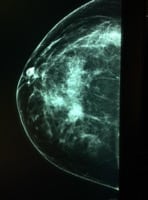

Mamografía. Una mamografía es una radiografía de la mama. Si se detecta una anormalidad en una mamografía de detección, tu médico puede recomendarte una mamografía de diagnóstico para realizar más evaluaciones de esa anormalidad.

• Cáncer de mama por mamografía